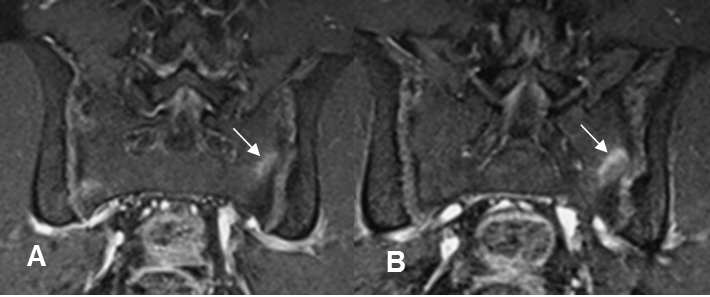

Fig 58 E. Espondilitis anquilosante.

A: Rx AP. Zona de esclerosis, sobre la sacroiliaca derecha.

B: RM axial en T1 y C: RM axial en STIR. La lesión es hipointensa en ambas secuencias, por fibrosis secundaria a lesión de evolución crónica.